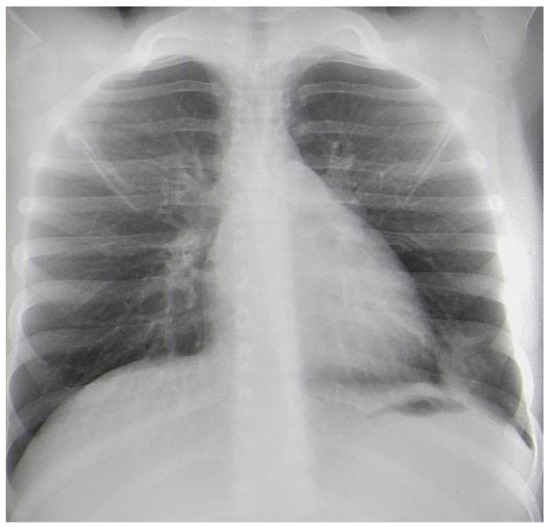

During the follow-up, the child had no complaints, and the physical examination was normal (Figure 6). The incision wounds healed primarily, and no complications were noticed. The patient recovered uneventfully. Annual physical and functional examinations of breathing will be conducted.

Figure 6. Frontal chest X-ray one month after the surgery.